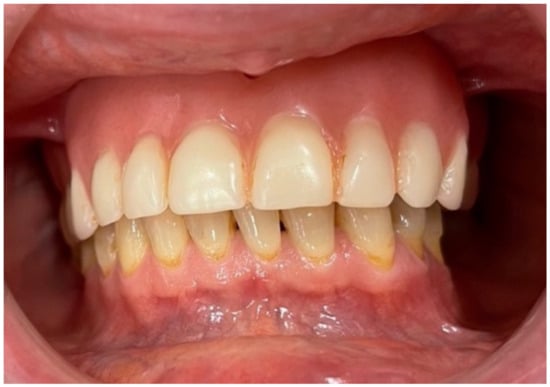

Case Report